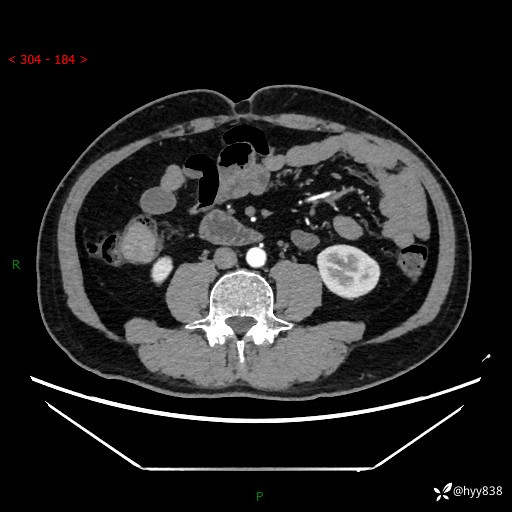

腹部CT增强扫描(外院CT平扫)

两期CT值:75hu 82hu